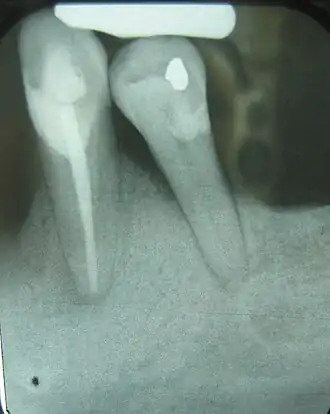

| Radiograph showing bone loss between the two roots of a tooth (black region). The spongy bone has receded due to infection under tooth, reducing the bony support for the tooth. | |